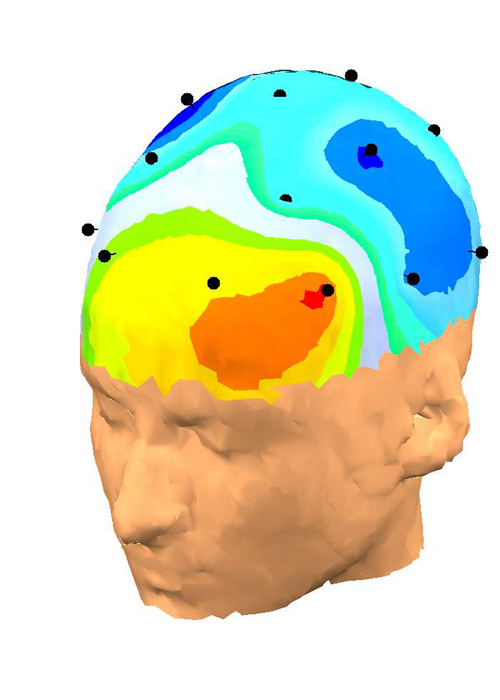

ȣȯ °¡´ÉÇÑ Á¦Ç° ¹®ÀÇÇϱâde-artifacted EEG´Â 󸮵Ǿî qEEG-Pro µ¥ÀÌÅͺ£À̽ºÀÇ °ü·Ã ¿¬·É´ë¿Í ºñ±³µË´Ï´Ù. sLORETA¸¦ »ç¿ëÇÏ¿© Linked Ears ¸ùŸÁÖ, Laplacian (CSP) ¹× ¼Ò½º À籸¼º ½ÅÈ£¿¡ ´ëÇÑ 3 °¡Áö pdf º¸°í¼°¡ ÀÛ¼ºµË´Ï´Ù. qEEG-Pro º¸°í¼´Â ´ÙÀ½°ú °°Àº ºÐ¼®À¸·Î ±¸¼ºµË´Ï´Ù.

• FFT Absolute Power (°í¼ÓǪ¸®¿¡º¯È¯ Àý´ë Àü·Â)

• FFT Relative Power (°í¼ÓǪ¸®¿¡º¯È¯ »ó´ë Àü·Â)

• Phase Coherence (À§»ó Àϰü¼º)

• Alpha peak detection (¾ËÆÄ ÇÇÅ© °ËÃâ)

• Amplitude Asymmetry (ÁøÆø ºñ´ëĪ)

• Phase Lag (À§»ó Áö¿¬)

• Comodulation (Cross-frequency power correlations) °øµ¿¼ö½Ä (±³Â÷ Á֯ļö Àü·Â »ó°ü)

• Burst Metrics (Max burst power, FWHM, Interburst Interval, Bursts per second) ¹ö½ºÆ® ¸ÞÆ®¸¯ (ÃÖ´ë ¹ö½ºÆ® Àü·Â, FWHM, ÀÎÅÍ ¹ö½ºÆ® °£°Ý, ÃÊ´ç ¹ö½ºÆ®)

• Extreme Z-score development (Age simulation analyses) * Àͽº Æ®¸² Z Á¡¼ö °³¹ß (¿¬·É ½Ã¹Ä·¹ÀÌ¼Ç ºÐ¼®)

• Power Fluctuation Analyses * Àü·Â º¯µ¿ ºÐ¼® *

• Percentage Deviant Activity * ÀÏÅ» Ȱµ¿ ¹éºÐÀ² *